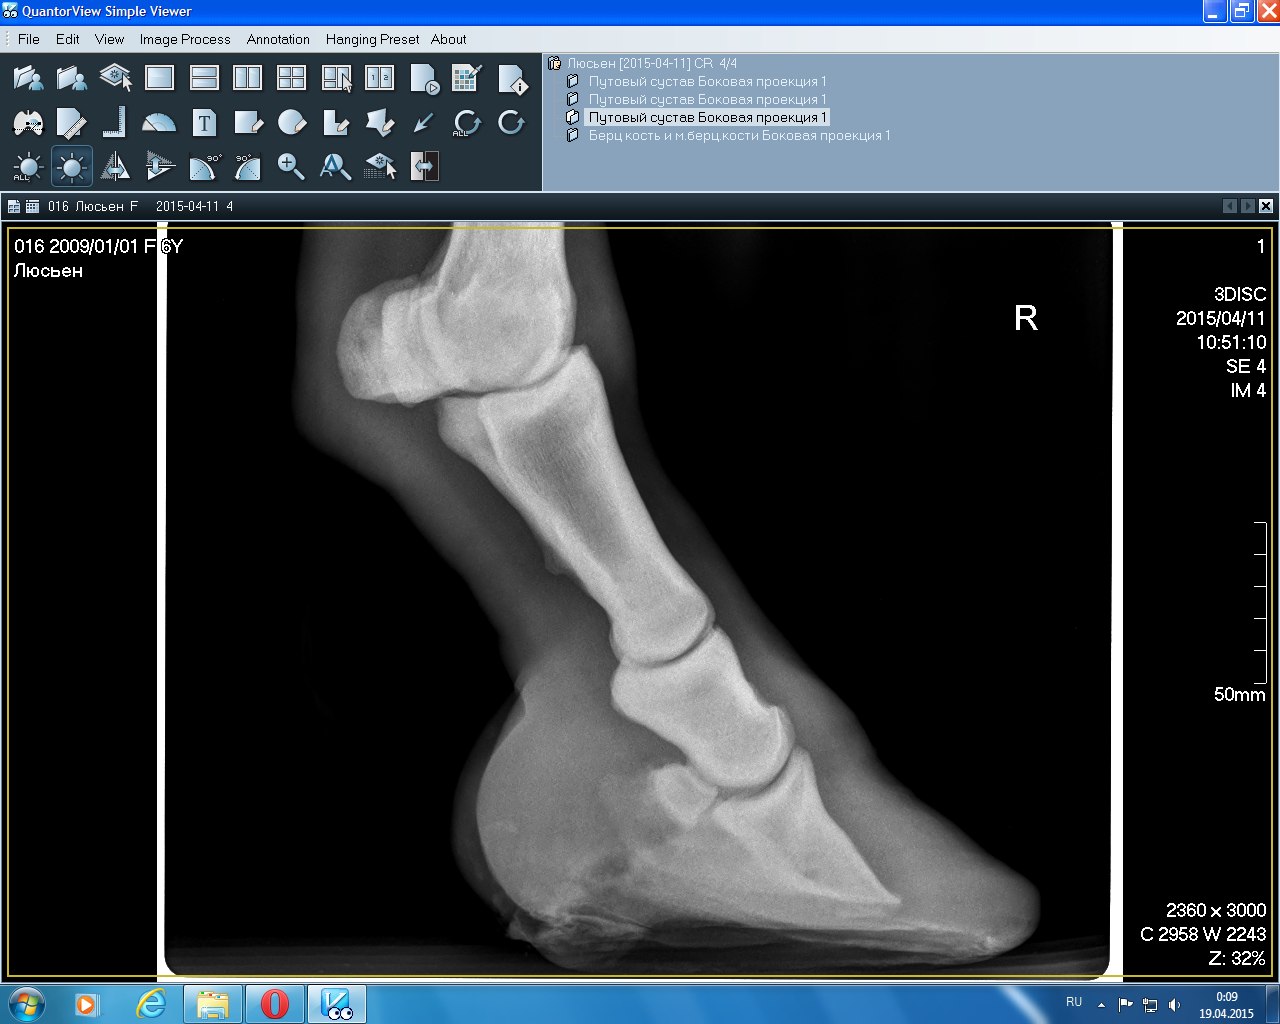

Правый перед(2015)